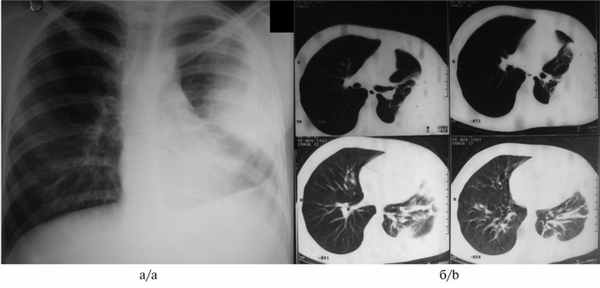

При поступлении предъявляла жалобы на общую слабость, снижение аппетита, одышку при физической нагрузке, повышение температуры до 37,8 °С. При обзорной рентгенографии легких (рис. 3, а) Рис. 3. Данные обследования больной Г. до операции. а — обзорная рентгенограмма органов грудной клетки (слева определяется субтотальная туберкулезная эмпиема плевры); б — компьютерные томограммы органов грудной клетки (в левой плевральной полости заднекостально располагается массивное осумкование густой жидкости). 20.11.07 выполнена ВАТС-плеврэктомия слева с декортикацией легкого (хирург Д.Б. Гиллер). слева определяется осумкованная эмпиема плевры. На компьютерных томограммах (см. рис. 3, б) в задних отделах левой плевральной полости массивное осумкование с выраженным уменьшением объема левого гемиторакса.

Для уточнения локализации и характера патологического процесса в этом случае помогает компьютерная томография (рис. 6, а). Рис. 6. Результаты обследования и лечения больной В., 17 лет, через 1 год после перенесенного плеврита. а — компьютерные томограммы органов грудной клетки (видны осумкования в правой плевральной полости); б — фотография операционного препарата (удаленный эмпиематозный мешок, на его разрезе жидкий казеоз). На компьютерных томограммах видны утолщения плевры и осумкования различной плотности.

Несмотря на ограниченный характер рентгенологических изменений и частое отсутствие клинических проявлений, в операционном препарате видна картина хронической туберкулезной эмпиемы с жидким казеозом и резким утолщением плевры (см. рис. 6, б).